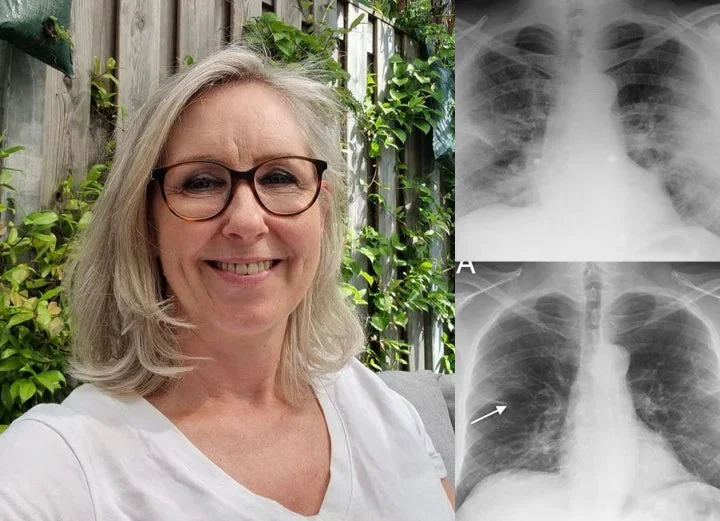

“l’ve spent most of my career on construction sites, constantly exposed to dust and airborne pollutants. Over time, it caught up with me-l developed COPD. At first, it was just mild shortness of breath, but the symptoms slowly worsened.l found myself coughing regularly, wheezing, and relying on an inhaler just to get through the day. Even climbing stairs became a challenge. My doctor warned me that if l didn’t take action, my condition could severely impact my quality of life.”

“By the fourth week, the tightness in my chest had lessened dramatically.l had more energy, and my doctor was surprised to see such a reduction in lung inflammation. Even my family noticedl wasn’t using my inhaler as much and seemed more active and upbeat.”

Now, seven weeks in, l can say with confidence that Mullein Aroma Diffuser has changed my life. My lungs feel stronger. The coughing,wheezing, and constant fatigue are gone.l can walk. play with my kids, and enjoy the outdoors again-without struggling to catch my breath. This product gave me back the ability to live fully.l recommend it to anyone battling COPD or breathing difficulties.lt brought me not just relief_but real hope.“

Max Winters- California

Hear From 150,000+ Satisfied Customers Who Cleared Their Lungs with BQYOOM™ Breatheora

“Living in a polluted city, I battled constant wheezing and exhaustion for years. Medications helped but made me feel drained. With BQYOOM™ Breatheora nasal inhalation, I felt my airways open up within 2 minutes of first use! My cough disappeared within two weeks, and breathing became much smoother. The instant relief is incredible.“

— Linda M., Age 52, ⭐⭐⭐⭐⭐

“After smoking for over a decade, climbing stairs left me breathless. I tried various remedies with no improvement until BQYOOM™ Breatheora nasal inhalation. I couldn’t believe how quickly I felt relief! After one week, I could walk up five floors without gasping. My constant cough vanished completely.“

— Bianca F., Age 47, ⭐⭐⭐⭐⭐

“With emphysema for ten years, every morning was a struggle with tight chest and constant mucus. Mullein teas helped a little, but BQYOOM™ Breatheora nasal inhalation gave me immediate soothing relief from the very first use. Within two weeks, I could walk my dog again without stopping.”

— Karen S., Age 68, ⭐⭐⭐⭐⭐